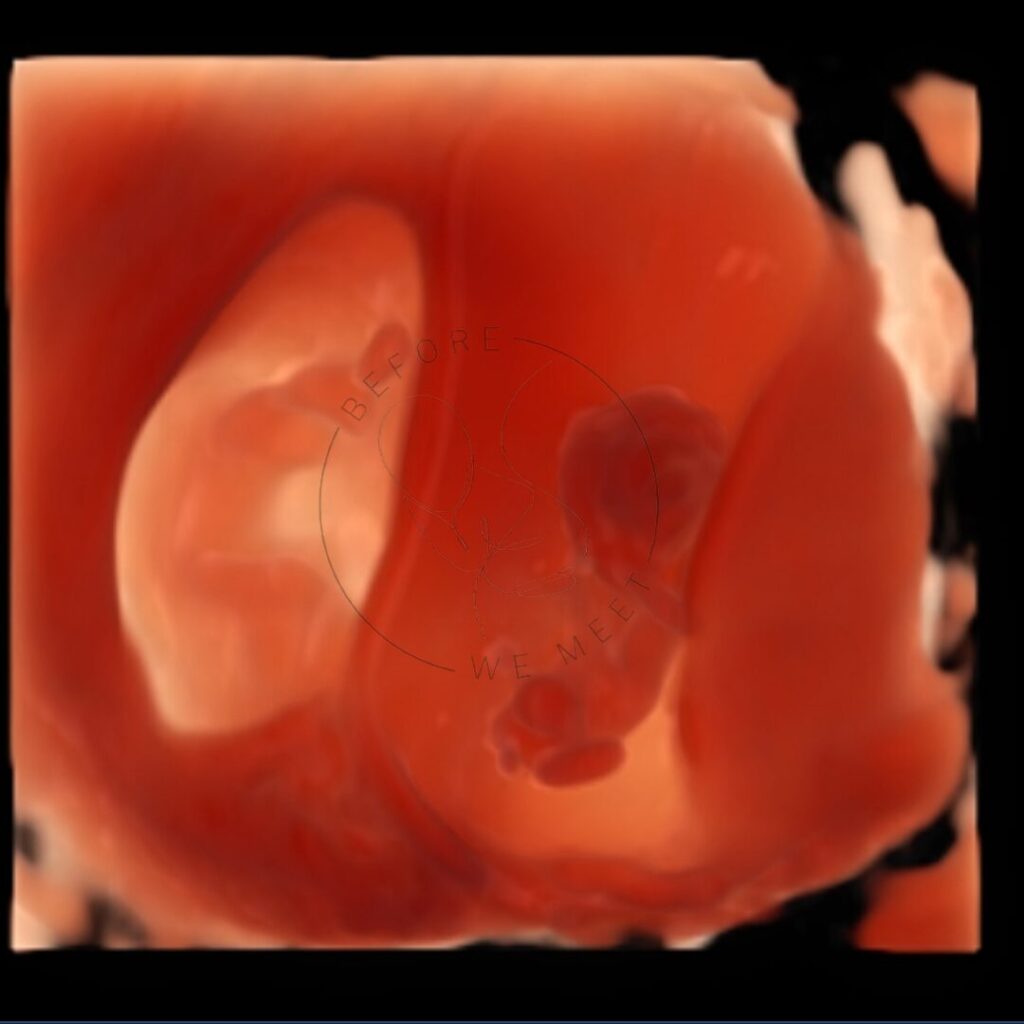

Veel ouders kiezen voor een pretecho als herinnering aan de zwangerschap of om samen met familie of vrienden extra naar de baby te kijken. Bij een 3D- of 4D-echo zien we duidelijk het gezichtje in kleur en zien we soms een lachje of een gaapje!

Een 3D/4D echo is éxtra bijzonder doordat we de baby met al zijn of haar details kunnen zien in stilstaande en bewegende beelden. Op wie lijkt zijn/haar neusje? Heeft hij/zij al bolle wangetjes? Of misschien zien we de baby zelfs wel drinken of lachen? Het laat jou (en ons!) verwonderen hoe magisch het nieuwe leven dat in je buik groeit is!

3D/4D echo